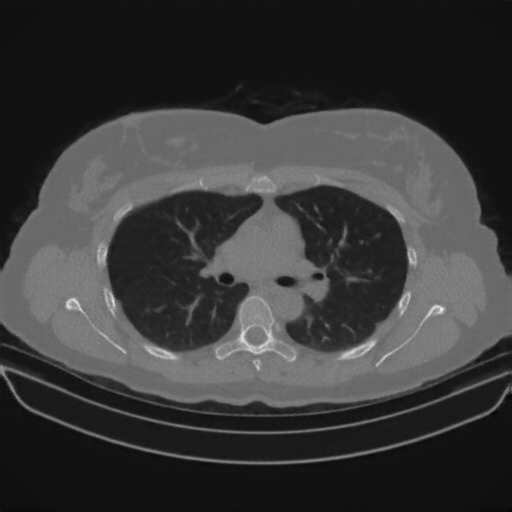

Slice 70 Targeting Evaluation

Slice: Slice_70

Slice Thickness: 1.5mm

Conversion: NATIVE β†’ VENOUS

Targeted Slice 70 - Network-Normalized Analysis (Generated vs Real Venous)

0.885

SSIM Score

0.092

RMSE

0.040

MAE

Average Network-Normalized Metrics Across All Slices (170 slices) - Generated vs Real Venous

0.886

SSIM Score (Avg)

0.097

RMSE (Avg)

0.041

MAE (Avg)

Targeted Slice 70 - HU-Space Analysis (Generated vs Real Venous)

HU SSIM

91.8

HU RMSE

40.2

HU MAE

Average HU-Space Metrics Across All Slices (170 slices) - Generated vs Real Venous

HU SSIM (Avg)

96.9

HU RMSE (Avg)

41.1

HU MAE (Avg)

Original NATIVE CT scan (input)

No window - Raw intensity values